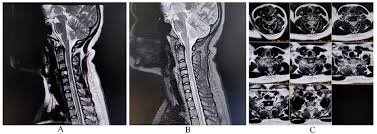

🧲 MRI Hallmarks – Quick Differentiation

📏 Longitudinal (≥3 segments)

- NMOSD

- Sarcoidosis

- Vascular congestion (dAVF)

- B12/copper deficiency

🎯 Posterior column–predominant

- B12

- Copper deficiency

- HIV vacuolar myelopathy

🧩 Patchy short lesions

- MS

🌲 Dorsal subpial enhancement

- Sarcoidosis (“Trident sign”)

🦉 Owl’s eyes

- Spinal cord infarction

🎯 Central gray matter involvement

- Viral (enteroviruses)

- Ischemia

- MOGAD

1️⃣ MRI with contrast

- Enhancement pattern

- Longitudinal extent

- Tract involvement